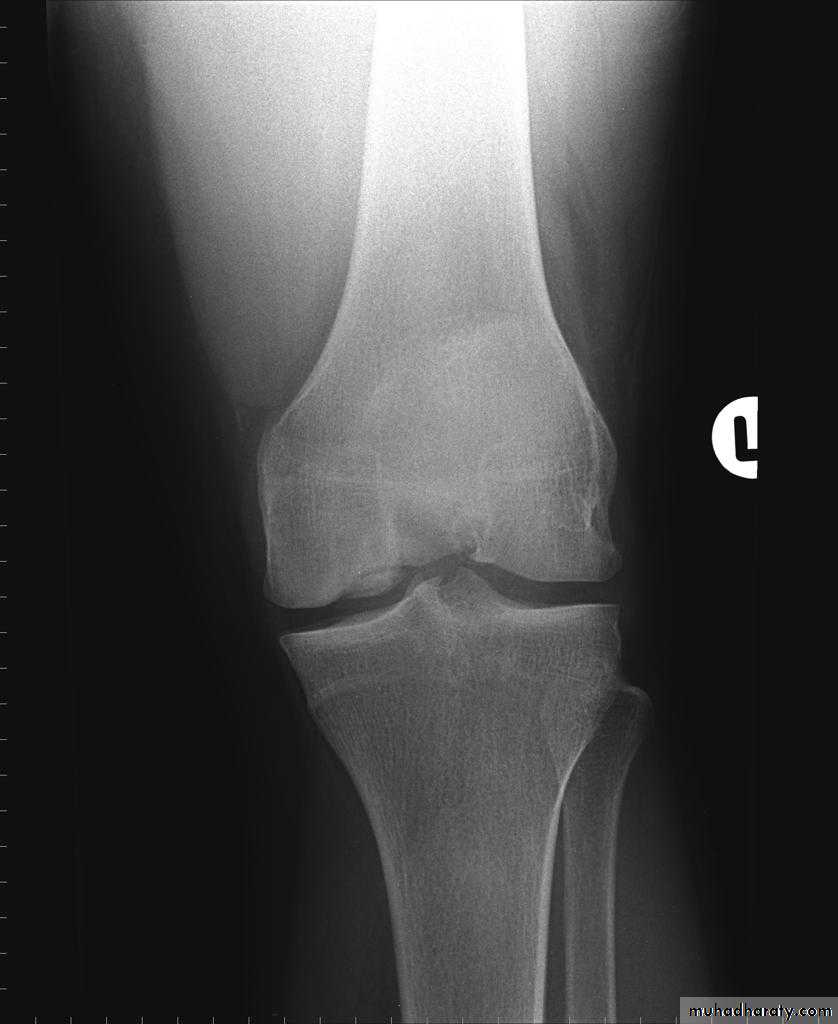

NEUROPATHIC ARTHRITIS (CHARCOT'S JOINT)

• Primary loss of sensation in a joint leads to arthropathy. Distribution helps determine etiology.• Causes

• Diabetes neuropathy: usually foot

• Tertiary syphilis : usually knee

• Syringomyelia: usually shoulder

• Radiographic features

• Common to all types

• *Joint instability: subluxation or dislocation

• *Prominent joint effusion

• --- Hypertrophic type, 20%

• Marked fragmentation of articular bone

• Much reactive bone

• --- Atrophic type, 40°/0

• Bone resorption of articular portion

• --- Combined type, 40%